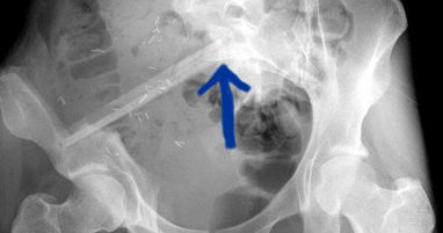

vermelden. Ich erinnert euch alle an die Bilder, die wir euch nach der Operation gezeigt haben. Hier ist es auf dem Foto noch einmal zu

sehen. Es ist ihr operativ das rechte Wadenbein aus dem Bein entfernt und als Stütze in das Becken eingesetzt worden, dort, wo vorher

die Beckenschaufel war. Das ist schon ein Meisterwerk ärztlicher Kunst gewesen. Und Gott hat Gelingen und Segen dazu gegeben. Die

Schmerzen, die Puschel in den letzten Tagen mehr hatte als sonst, rühren jetzt daher, dass der Knochen etwa an der Stelle, auf die der

Pfeil zeigt, richtiggehend durchgebrochen ist. Die Ärzte sprechen von einem Ermüdungsbruch. Der Knochen ist in der Substanz während

der Zeit der Chemo und der dadurch beabsichtigten Verhinderung der Neubildung von Zellen (Zielpunkt waren natürlich die

Krebszellen) zurückgegangen und ermüdet. Das große Problem ist, dass nun noch weniger Stabilität da ist und der Knochen erst wieder

zusammenwachsen muss. Darum werdet ihr, wenn ihr hier reinschaut, nun wieder mehr Bilder von “Puschel im Liegen” sehen. Das ist